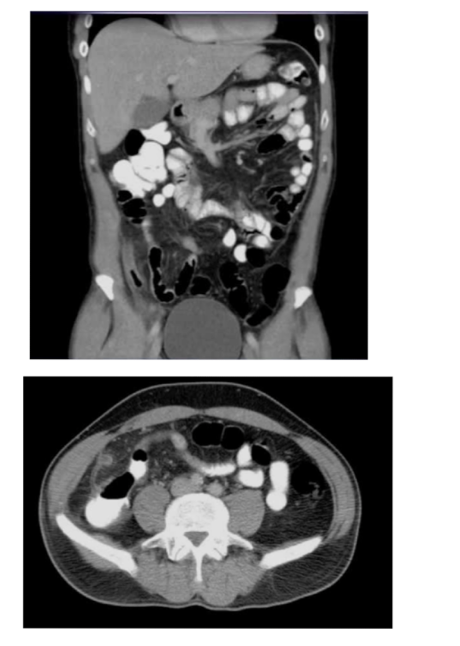

What is the pathology?

• Ascites: abnormal

collection of

intraperitoneal fluid

• Evidenced by the fluid within the recesses of

peritoneal cavity